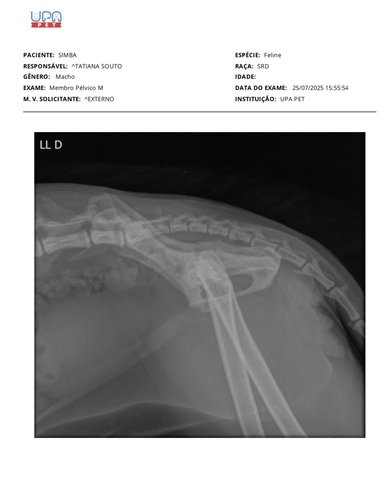

Fizemos exames e o hemograma mostrou alterações inflamatórias e imunológicas, que sugerem que o corpo dele está lutando contra algo sério. Além disso, o exame de sangue revelou problemas no fígado e uma glicose muito alta, que pode indicar diabetes ou estresse extremo devido à dor. Também foi constatado o início de uma osteoporose que causou uma uma hérnia de disco. E pra finalizar descobrimos uma úlcera na boca que está fazendo ele não querer se alimentar nem beber água.

Hoje 29/07 Simba retornou da internação, foi constatado que ele tem uma artrose degenerativa na lombar.

Ele não pode mais subir e descer dos lugares, precisa de ajuda para não piorar a condição. Com o tempo a evolução da doença pode causar perda total dos movimentos traseiros, se não for tratado.

Preciso de ajuda para dar seguimento ao tratamento dele: consulta com ortopedista, fisioterapia e se não resolver vai precisar operar.